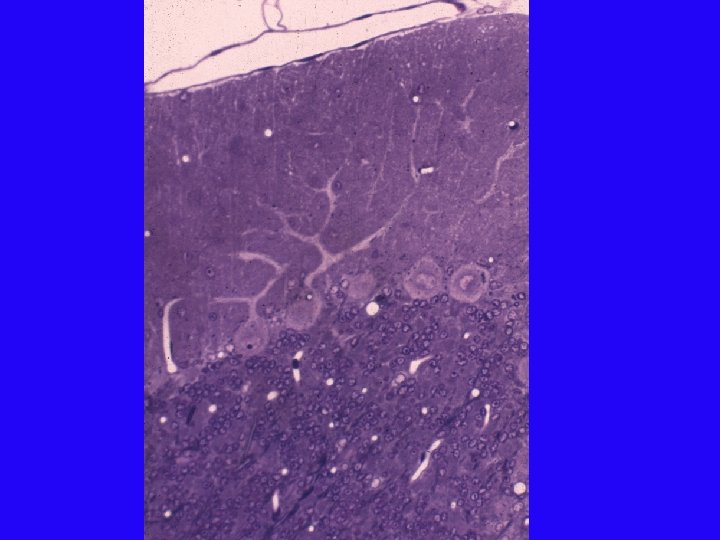

Corpus callosum agenesis in FAS patients Control Thin c. callosum Absent c. callosum (From Mattson et al. , 1994)

MR images of 9 -year old girl with FAS C. callosum agenesis Colpocephaly Courtesy of Dr. Sarah Mattson, SDSU

Brain Size Changes in FAS Courtesy of Dr. Sarah Mattson, SDSU